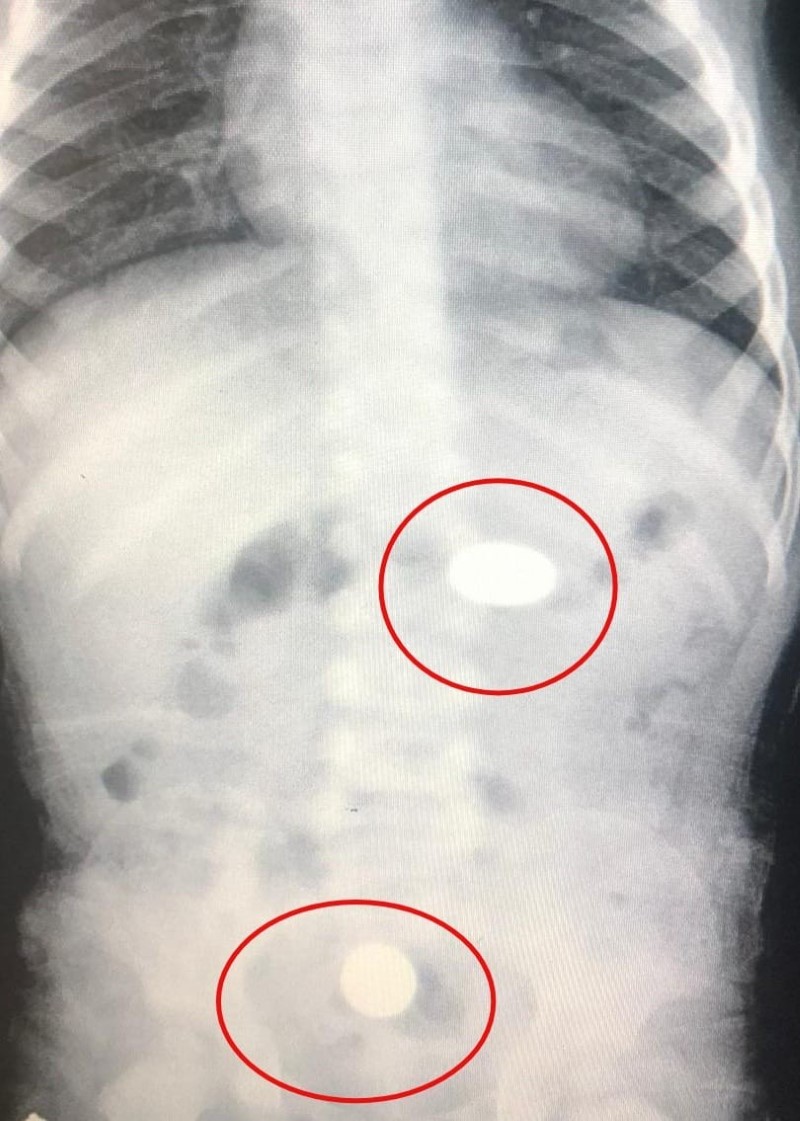

Yapılan tetkiklerde paralardan birinin bebeğin midesinde, diğerinin ise yemek borusunda kaldığı tespit edildi. Sağlık durumunun iyi olduğu belirtilen Murat Y., tedaviye alındı.